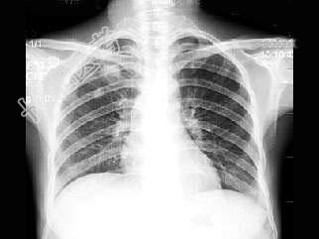

- 单项选择题男,29岁, 体检胸片如图,最可能的诊断是 ( )

A、右上肺炎症

B、右上肺炎性假瘤

C、右上肺结核瘤

D、右上肺肿瘤

E、结节病